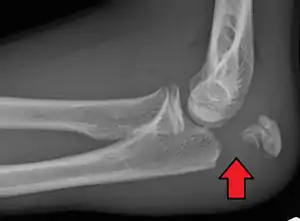

Olecranon fracture

| Fracture of the olecranon | |

To assess an olecranon fracture, a careful skin exam is performed to ensure there is no open fracture. Then a complete neurological exam of the upper limb should be documented.[5][2] Frontal and lateral X-ray views of the elbow are typically done to investigate the possibility of an olecranon fracture.[1] A true lateral x-ray is essential to determine the fracture pattern, degree of displacement, comminution, and the degree of articular involvement.